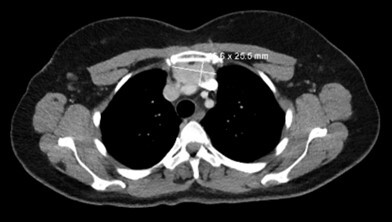

Ectopic thyroid tissue is rare in the general population and more prevalent in people who have existing thyroid disease. Common anatomical sites of ectopic thyroid tissue include the lateral cervical region, thyroglossal duct, mediastinum, lingual, sublingual, and submandibular region. Intrathymic ectopic thyroid tissue is exceedingly rare. The purpose of this report is to describe one such case in a 52-year-old African-American female with Graves' disease. The patient presented for a physical exam and follow-up. During the exam, an incidental mediastinal mass was discovered, which was evaluated by imaging studies and subsequently was resected. Histologically, the mass was composed of variable-sized thyroid follicles lined by a monolayer of cuboidal to columnar follicular epithelial cells and filled with eosinophilic colloid, surrounded by a rim of unremarkable compressed thymic tissue.